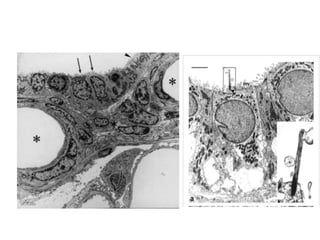

GLOMERULAR FILTRATION :- The

Glomerular Filtration Barrier Has

Three Layers

(1) the endothelium of the

capillary,

(2) a basement membrane,

and

(3) a layer of specialized

epithelial cells (podocytes)

of the capsule surrounding

the outer surface of the

capillary basement

membrane

GLOMERULAR FILTRATION :- The Glomerular Filtration Barrier Has Three

Layers But still high filtration rate ?

The high filtration rate across the

glomerular capillary membrane

• Endothelium of the

glomerular capillaries is

fenestrated

• Although the fenestrations are

relatively large, endothelial

cells are richly endowed

with fixed negative

charges that hinder the

passage of plasma proteins

Basement

membrane:

 consists of a meshwork of collagen

and proteoglycan fibrillae through

which large amounts of water and small

solutes can filter.

 effectively prevents filtration of plasma

proteins, in part because of strong

negative electrical

charges associated with

the proteoglycans

Podocyte :

• These cells are not continuous but have long

footlike processes (pedicels) that encircle the

outer surface of the capillaries.

• pedicels interdigitate to form

filtration slits wide along the capillary

wall.

• Extremely thin processes

called slit diaphragms bridge

the slits between the pedicels

• The epithelial cells, which also have

negative charges, provide additional

restriction to filtration of plasma proteins

Slit Diaphragm as rungs of ladder between

Foot processes of 2 adjacent podocytes

Spaces between slit diaphragms

constitute the path through which

the filtrate, travels to enter

Bowman’s space.

• while the basement membrane may

contribute to the selectivity of the filtration

barrier, integrity of the slit diaphragms is

essential to prevent excessive leak of plasma

protein (albumin). Some protein-wasting

diseases are associated with abnormal slit

diaphragm structure